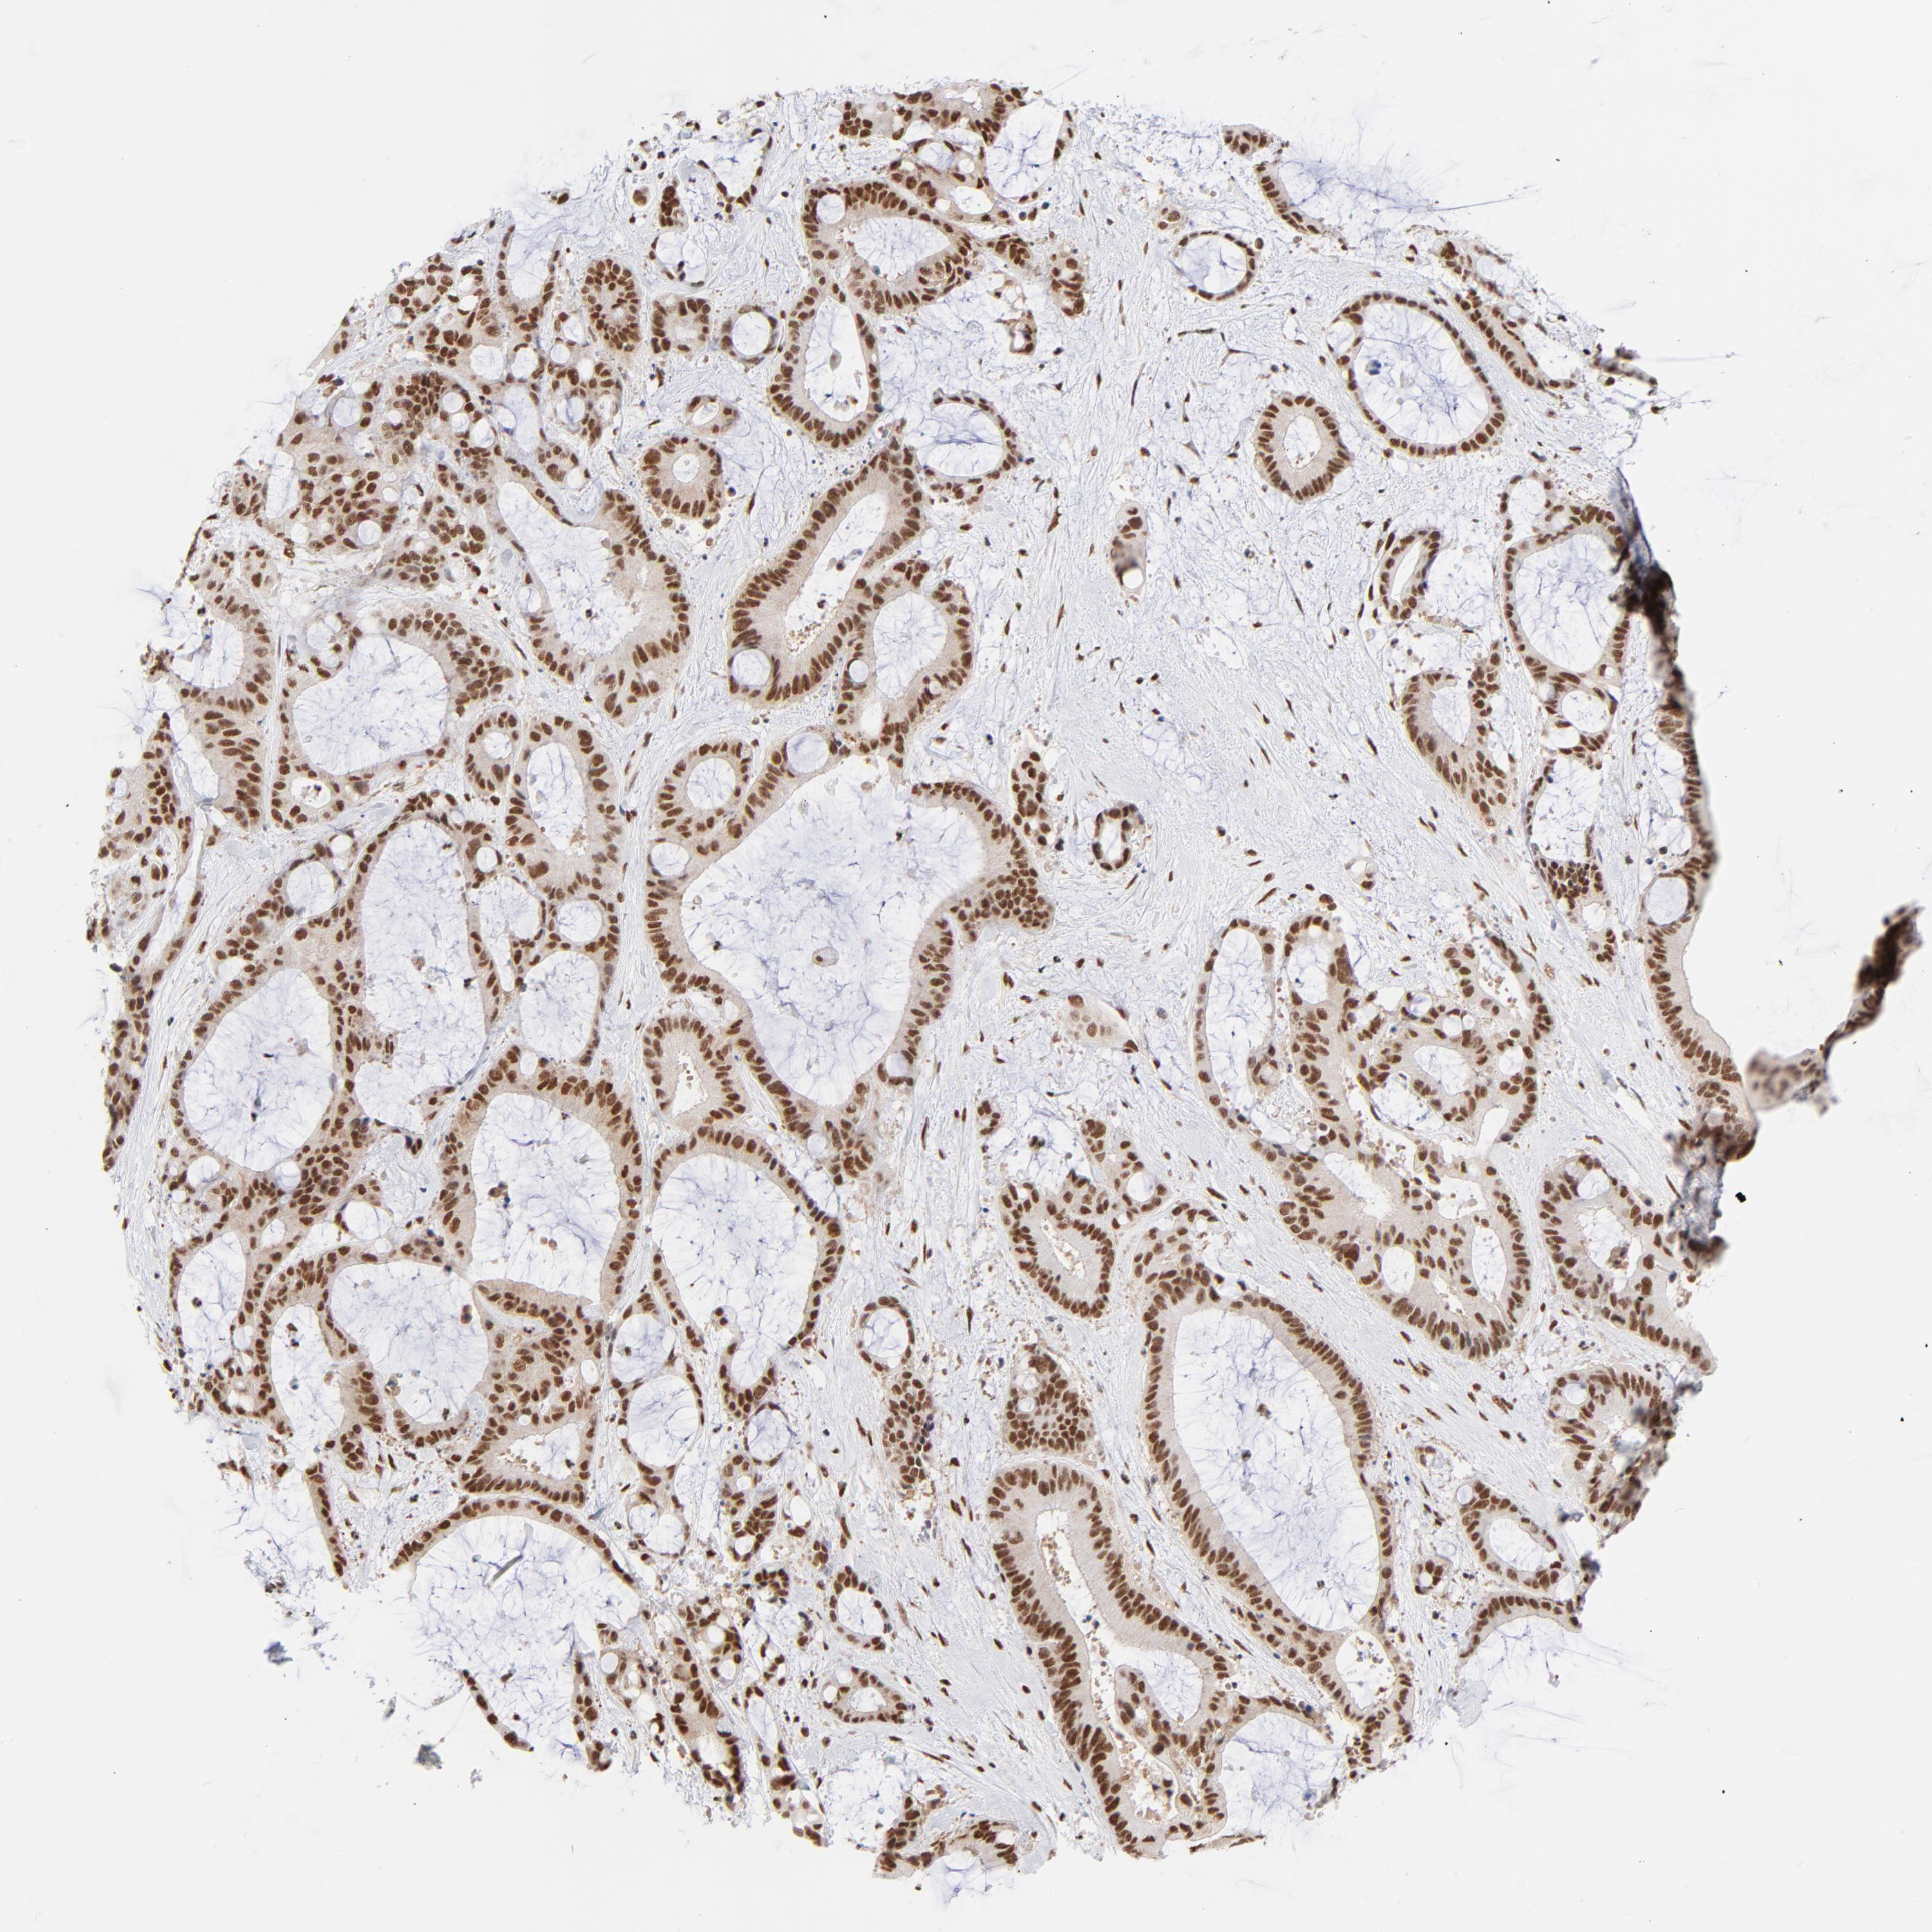

LIVER CANCER - Protein expressioni

A mouse-over function shows sample information and annotation data. Click on an image to view it in a full screen mode. Samples can be filtered based on level of antibody staining by selecting one or several of the following categories: high, medium, low and not detected. The assay and annotation is described here.

Note that samples used for immunohistochemistry by the Human Protein Atlas do not correspond to samples in the TCGA dataset.

Antibody stainingi

Antibody staining in the annotated cell types in the current human tissue is reported as not detected, low, medium, or high, based on conventional immunohistochemistry profiling in selected tissues. This score is based on the combination of the staining intensity and fraction of stained cells.

Each image is clickable and will lead to virtual microscopy that enables deeper exploration of all samples and also displays staining intensity scores, fraction scores and subcellular localization as well as patient and tissue information for each sample.

Antibody HPA019150

Antibody CAB003803

Staining

High

Medium

Low

Not detected

Intensity

Strong

Moderate

Weak

Negative

Quantity

>75%

75%-25%

<25%

None

Location

Nuclear

Cytoplasmic/membranous

Cytoplasmic/membranous,nuclear

Cholangiocarcinoma

Carcinoma, Hepatocellular, NOS